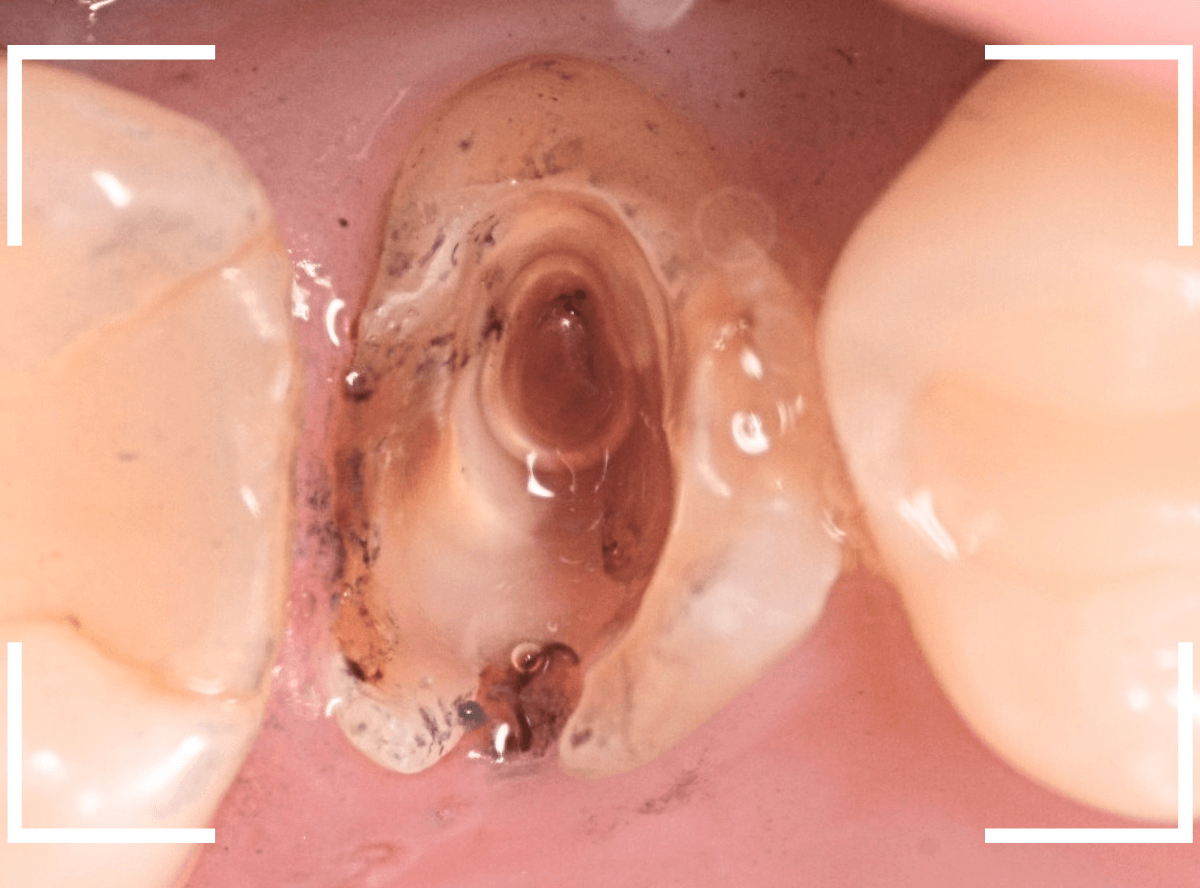

まず、土台の治療をしてから時間が経過していることと、不適合になっている事から、外して中を調べます。

すると、土台の中で虫歯にもなっていました。

(〇部の赤い部分)

こういった事は、レントゲン写真でもよくわからない事が多く、土台を外す治療は本当に神経を使います。

今回は、歯肉の中まで歯が欠損しているので、このまま土台とさし歯を作り直しても、いい結果にはなりません。

患者さんに状況を説明し、歯の周りの歯肉を麻酔をして電気メスでトリミングします。

このように歯の際が歯肉からしっかり出てる状況で製作しないと、さし歯はしっかりお口の中で安定しません。

この状態で新しい土台(ファイバー・コア)の型を取ります。